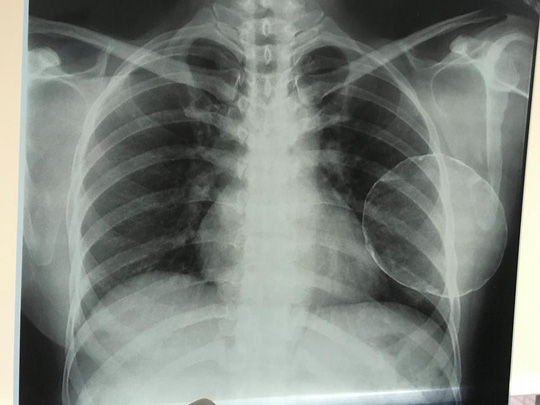

Kết quả siêu âm và chụp X quang cho thấy tình trạng ngực trái bị co thắt và vôi hóa hoàn toàn (can-xi hóa), các bác sĩ đã quyết định mổ cắt bỏ hoàn toàn khối vôi hóa, đồng thời tái tạo lại thành ngực sau 3 giờ mổ.

Theo BS Tú Dung, co thắt bao xơ sau nâng ngực chiếm tỷ lệ không cao nhưng đa phần gây khó chịu cho bệnh nhân, đặc biệt là yếu tố thẩm mỹ.

Bà O. được phẫu thuật bỏ khối vôi hóa trong ngực